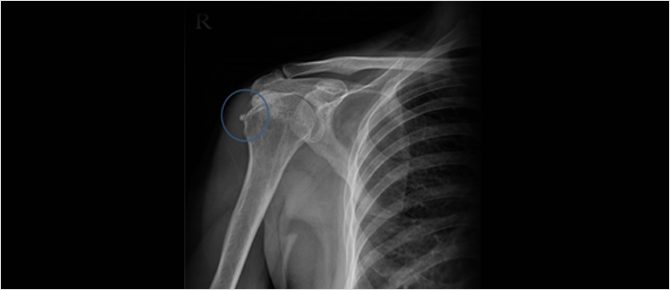

석회성 건염 X-ray

석회성 건염은 X-ray 촬영을 통해 힘줄에 생긴 석회질을 확인하는 방법으로 진단이 가능합니다.